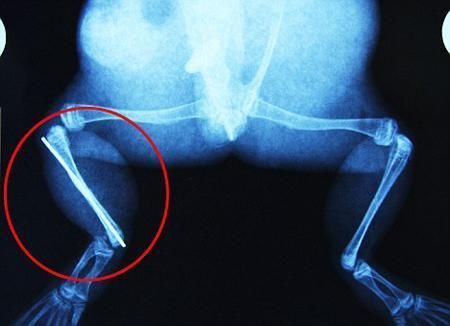

布魯萊的主人,居住在南非約翰內(nèi)斯堡附近的62歲的安妮·米恩斯說(shuō):“我對(duì)這只青蛙如此關(guān)心,人們一定認(rèn)為我瘋了,但是我無(wú)法眼睜睜看著它那么痛苦。青蛙因其靈活的腿腳而著稱(chēng),一想到布魯萊的腿里要留下一個(gè)薄金屬片,我就感到心痛。然而我知道,如果不進(jìn)行手術(shù),布魯萊以后就沒(méi)辦法動(dòng)彈了。因此我匆匆趕到獸醫(yī)那里,央求他給這只可憐的青蛙動(dòng)手術(shù)。這位獸醫(yī)整天救助小貓小狗,他很難理解為什么我這么擔(dān)心一只青蛙,但是最終他還是答應(yīng)了給布魯萊做手術(shù)。手術(shù)后是幾個(gè)小時(shí)的焦急等待,我們希望它能快快蘇醒過(guò)來(lái)。不過(guò)現(xiàn)在它的傷口已經(jīng)愈合,又能在花園里跳來(lái)跳去了。X光照射顯示,它會(huì)恢復(fù)的跟以前一樣!

野生生物專(zhuān)家安妮經(jīng)常為學(xué)校寫(xiě)教材,她認(rèn)為這是人類(lèi)第一次通過(guò)手術(shù)給一只青蛙接斷腿。在手術(shù)開(kāi)始階段,獸醫(yī)把少量給狗用的麻醉藥注入到這只青蛙體內(nèi),讓它失去知覺(jué)。然后他在布魯萊的斷腿上切開(kāi)一個(gè)小口,把一根小鋼針植入腿里。最后獸醫(yī)給它縫了9針,把切口縫合在一起。僅僅幾周后,布魯萊就能在安妮家附近活動(dòng)了。這只青蛙大約已有25歲,主要以嚙齒動(dòng)物、蛇和其他青蛙為食。布魯萊所屬的牛蛙種群正在不斷減小,目前只能在非洲南部的濕地里才能看到這種青蛙。

安妮有2個(gè)孩子,她已經(jīng)從事20多年兩棲動(dòng)物保護(hù)工作。她認(rèn)為鄰居家的狗狗在把布魯萊從地下刨出來(lái)的時(shí)候,它正在地下冬眠、她說(shuō):“世界上只有這個(gè)地區(qū)能看到這種牛蛙,這種青蛙現(xiàn)在變得越來(lái)越稀少。因?yàn)槲覐氖乱吧锉Wo(hù)工作,因此認(rèn)識(shí)很多兩棲動(dòng)物專(zhuān)家,但是以前他們誰(shuí)也沒(méi)見(jiàn)過(guò)這種事情?吹讲剪斎R越來(lái)越健康我非常開(kāi)心。現(xiàn)在還需要一段時(shí)間,它的金屬腿和它的骨骼才能融為一體,那時(shí)布魯萊會(huì)跟以前一樣健康。我們認(rèn)為這個(gè)過(guò)程需要幾周時(shí)間,但是一旦它完全康復(fù),我希望把它放歸大自然,讓它重新回到它最鐘愛(ài)的濕地里!